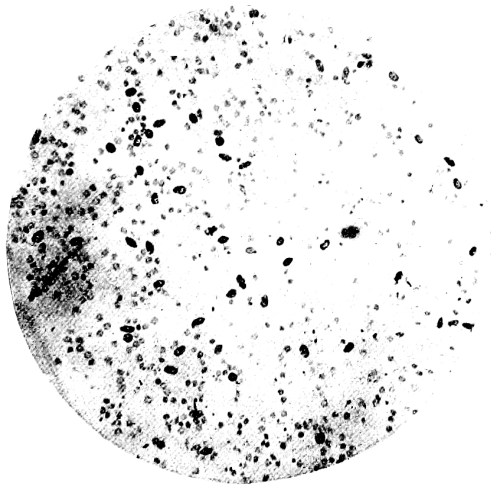

8. Measurement of Blood Corpuscles (human) 97

9. Measurement of Blood Corpuscles (sheep) 97

10. Photo-micrograph of Red Blood Corpuscles from Domestic Fowl 99

11. Photo-micrograph of Blood Corpuscles of Fish 99

12. Photo-micrograph of Blood Corpuscles from a Dried Stain of the Blood of a Cod-fish 100

13. Photo-micrograph of a Frog‘s Blood showing oval nucleated Red Corpuscles 101

14. Photo-micrograph of Crystals of Hæmin 102